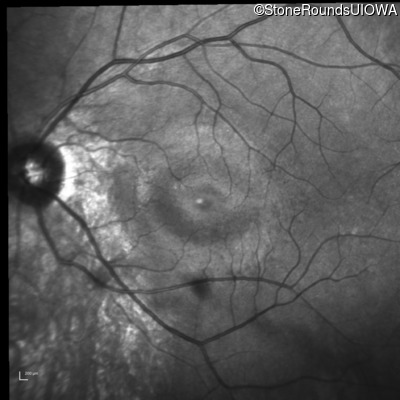

Infrared Fundus Photograph - Right - 20/20

Exemplar

Infrared Fundus Photograph - Left - 20/20 -2